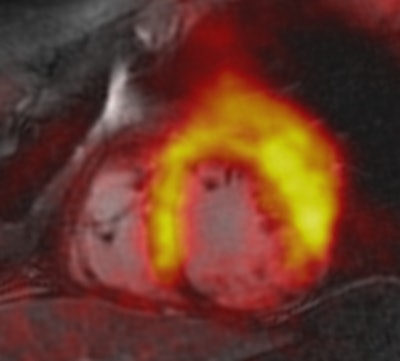

There was good agreement between PET and late gadolinium enhancement and PET and cine imaging, the researchers found. With PET, 31% of the myocardial segments showed a decrease in FDG tracer uptake, indicating an infarcted area. With late gadolinium enhancement, 28% of the infarcted myocardial segments were visible, and 24% of the segments showed abnormal wall motion with cine imaging.

To better evaluate the quantitative imaging results, Nensa and colleagues developed in-house software to generate coregistered images, which compared late gadolinium-enhanced images with results from FDG-PET. Using the software in a separate group of 15 patients with visually conclusive agreement between PET and late gadolinium enhancement results, the researchers found PET defect size (35 mL) to be significantly larger than the late gadolinium-enhanced defect size (27 mL).